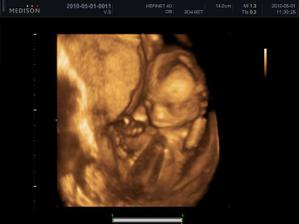

Laurinkin braček Marko

autor@williamjozef - sama sa cudujem ze kde sa taky velky chlapisko vmestil, pridam aj fotku kde som 12hod pred porodom-tam je to brucho myslim o dost vatsie,ja som totiz priberala az posledny mesiac.